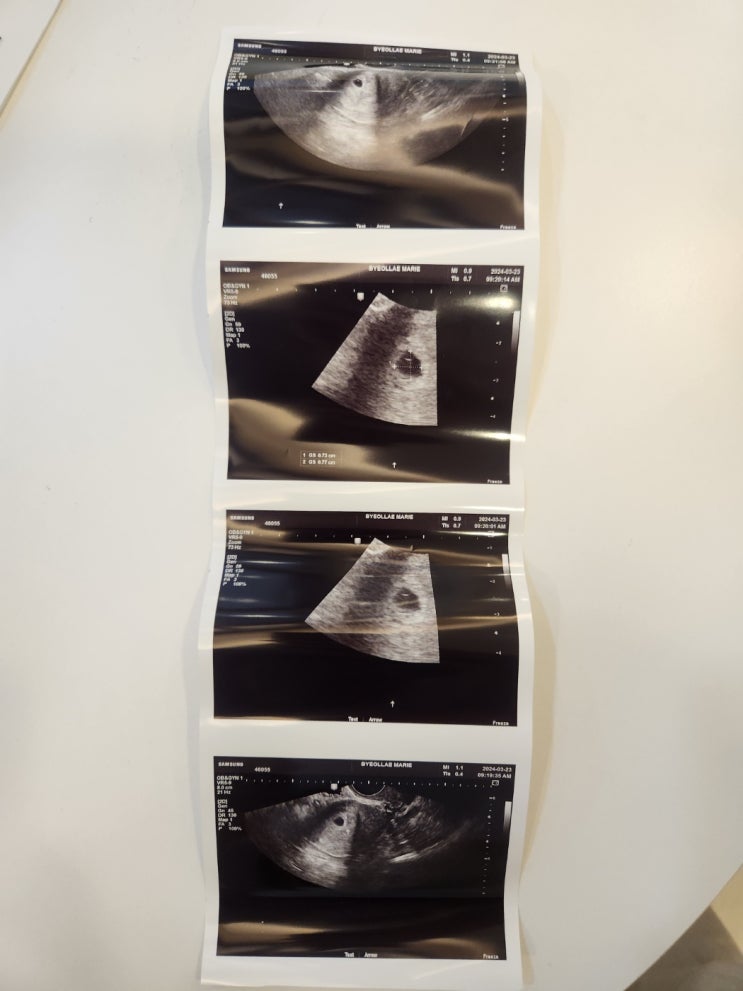

다낭성 난소증후군 자연임신 일기/임신 6-8주차 별 증상

이 글을 쓰는 시점은 벌써 8주차가 반이나 지났다! 하루하루가 어찌 흐르는지 모르겠다 ㅎㅎㅎㅎㅎ 아직도 ...

다낭성난소 증후군이 자연임신 된 이야기[내가 느낀 임신 3주차-5주차 별 증상]

나는 술을 너무나 좋아하는 애주가 이고 현재는 연애 2년반 결혼8년차 부부이다 사실 나는 고등학교때부터 ...